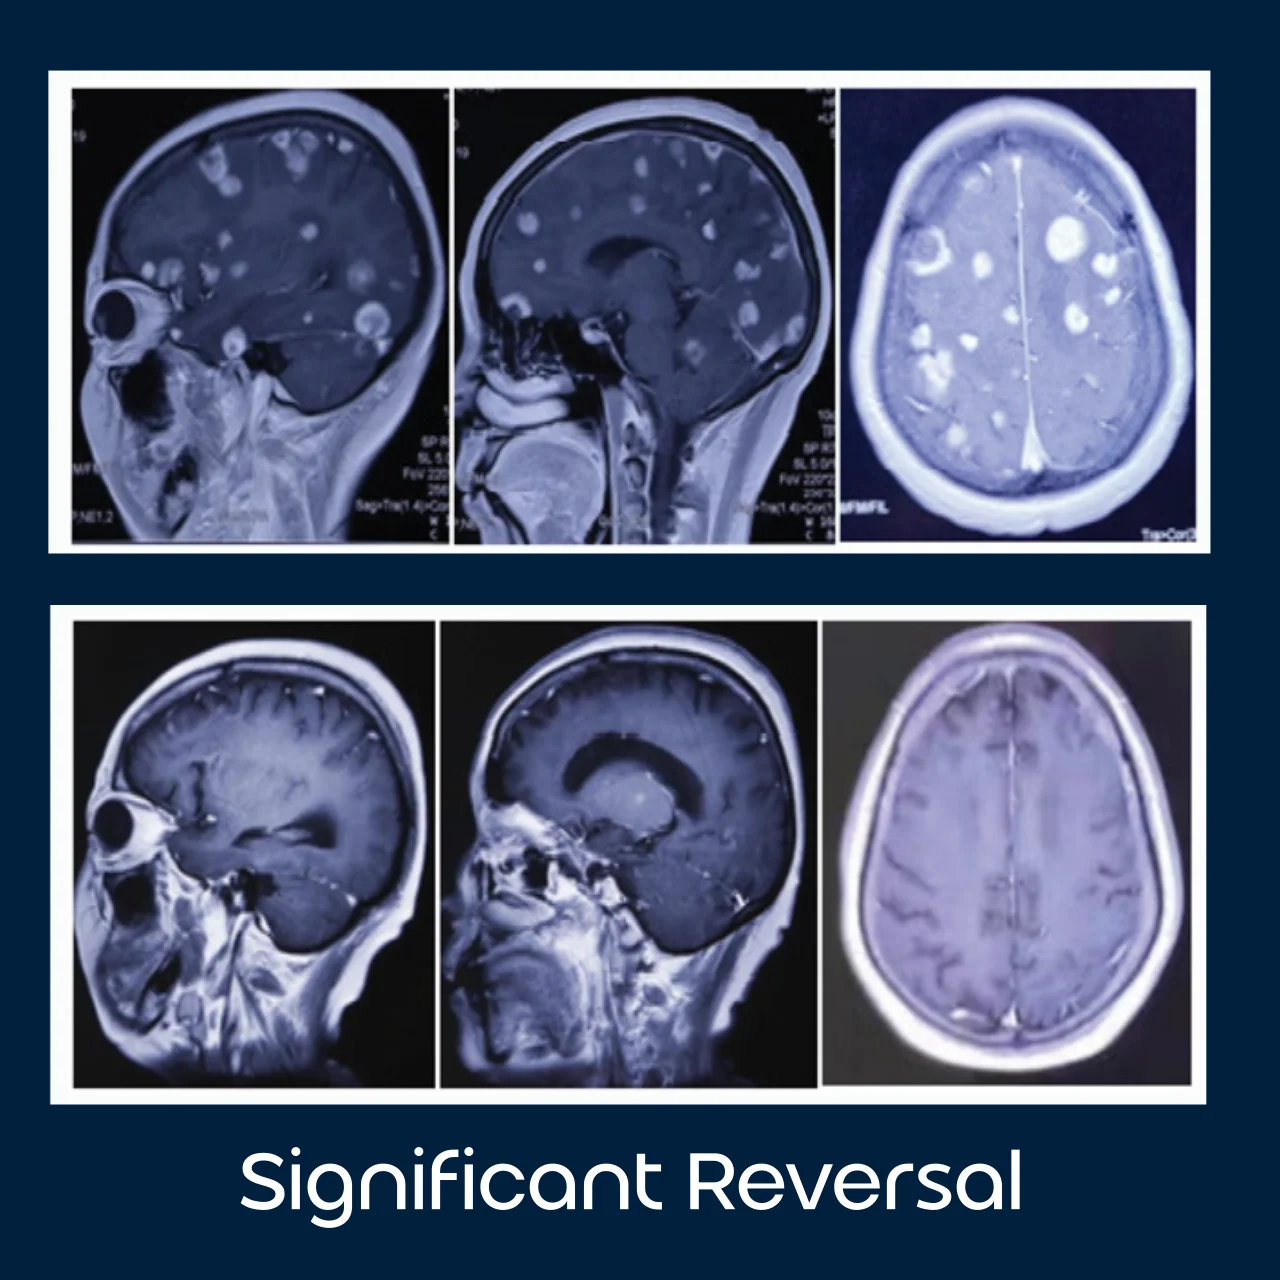

Significant

Reversal

82 advanced

cancer patients

- Brain Metastases Completely Disappear in Non-Small Cell Lung Cancer Using Hydrogen Gas Inhalation: A Case Report